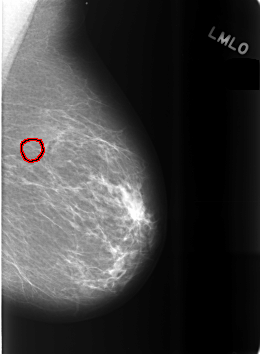

C_0483_1.LEFT_MLO

LEFT_MLO LINES 5656 PIXELS_PER_LINE 4152 BITS_PER_PIXEL 12 RESOLUTION 50 OVERLAY

FILE: C_0483_1.LEFT_MLO.OVERLAY

TOTAL_ABNORMALITIES 1

ABNORMALITY 1

LESION_TYPE CALCIFICATION TYPE PLEOMORPHIC DISTRIBUTION CLUSTERED

ASSESSMENT 4

SUBTLETY 4

PATHOLOGY BENIGN

TOTAL_OUTLINES 1

BOUNDARY